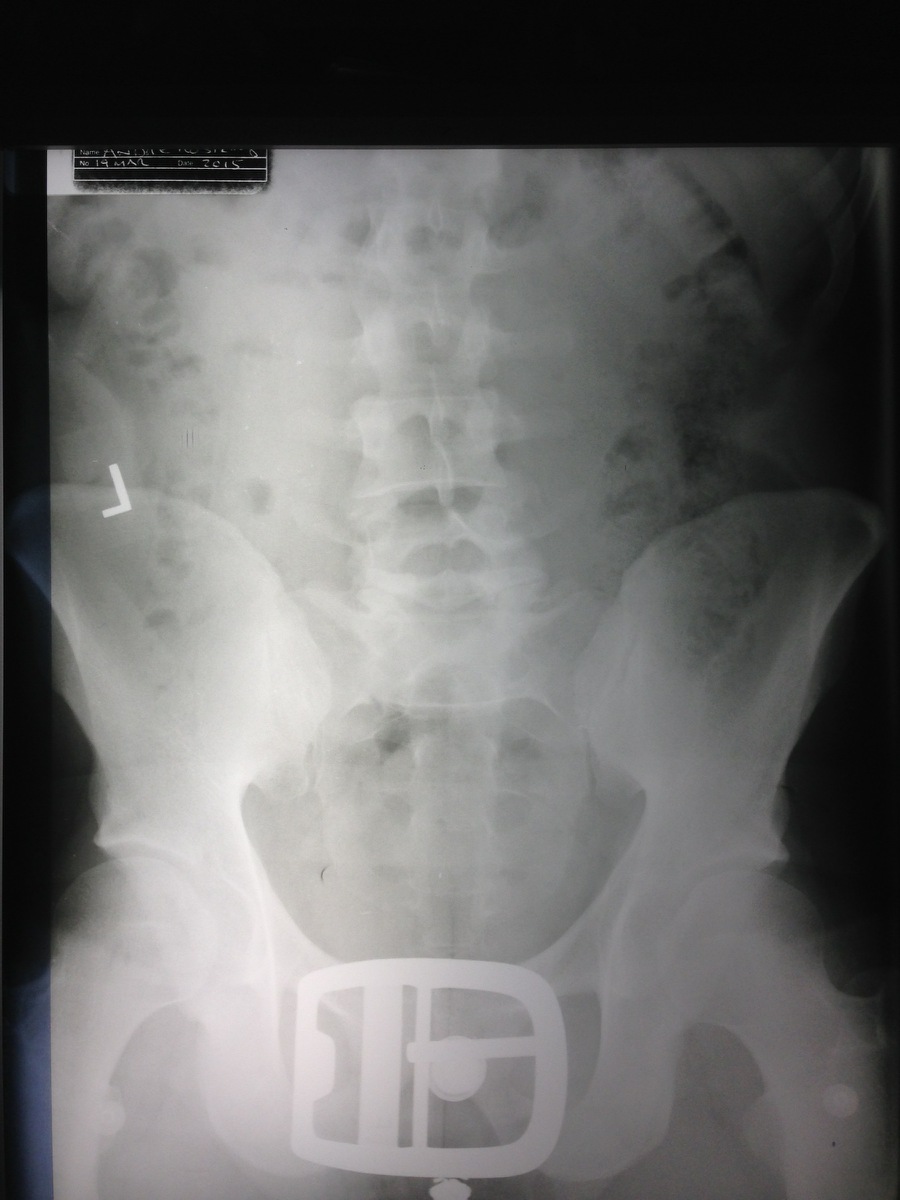

Album List » 2015_Andre » LS-Andre.jpg (151/151)

Original Image (900x1200)